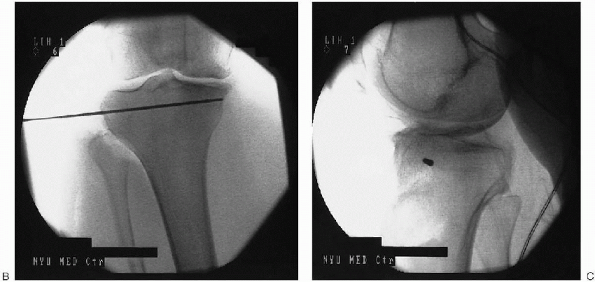

joint line in the coronal plane. This is done by laying a wire anterior

to the surface of the knee and is confirmed by fluoroscopy (Fig. 27-4).

The cutaneous landmarks are then marked with a surgical pen on the

anterior tibial surface. A second K-wire is subsequently dragged

distally in a parallel fashion so as to lie 5 to 10 mm below the margin

of the tibial plateaus. Cutaneous landmarks are again drawn. This level

represents the proximal fixation margin. Under fluoroscopic guidance, a

K-wire is inserted at the selected level, aiming medially from the

lateral side (Fig. 27-5). This wire serves as a

![]() |

FIGURE 27-4. Fluoroscopic determination of proximal fixation level.